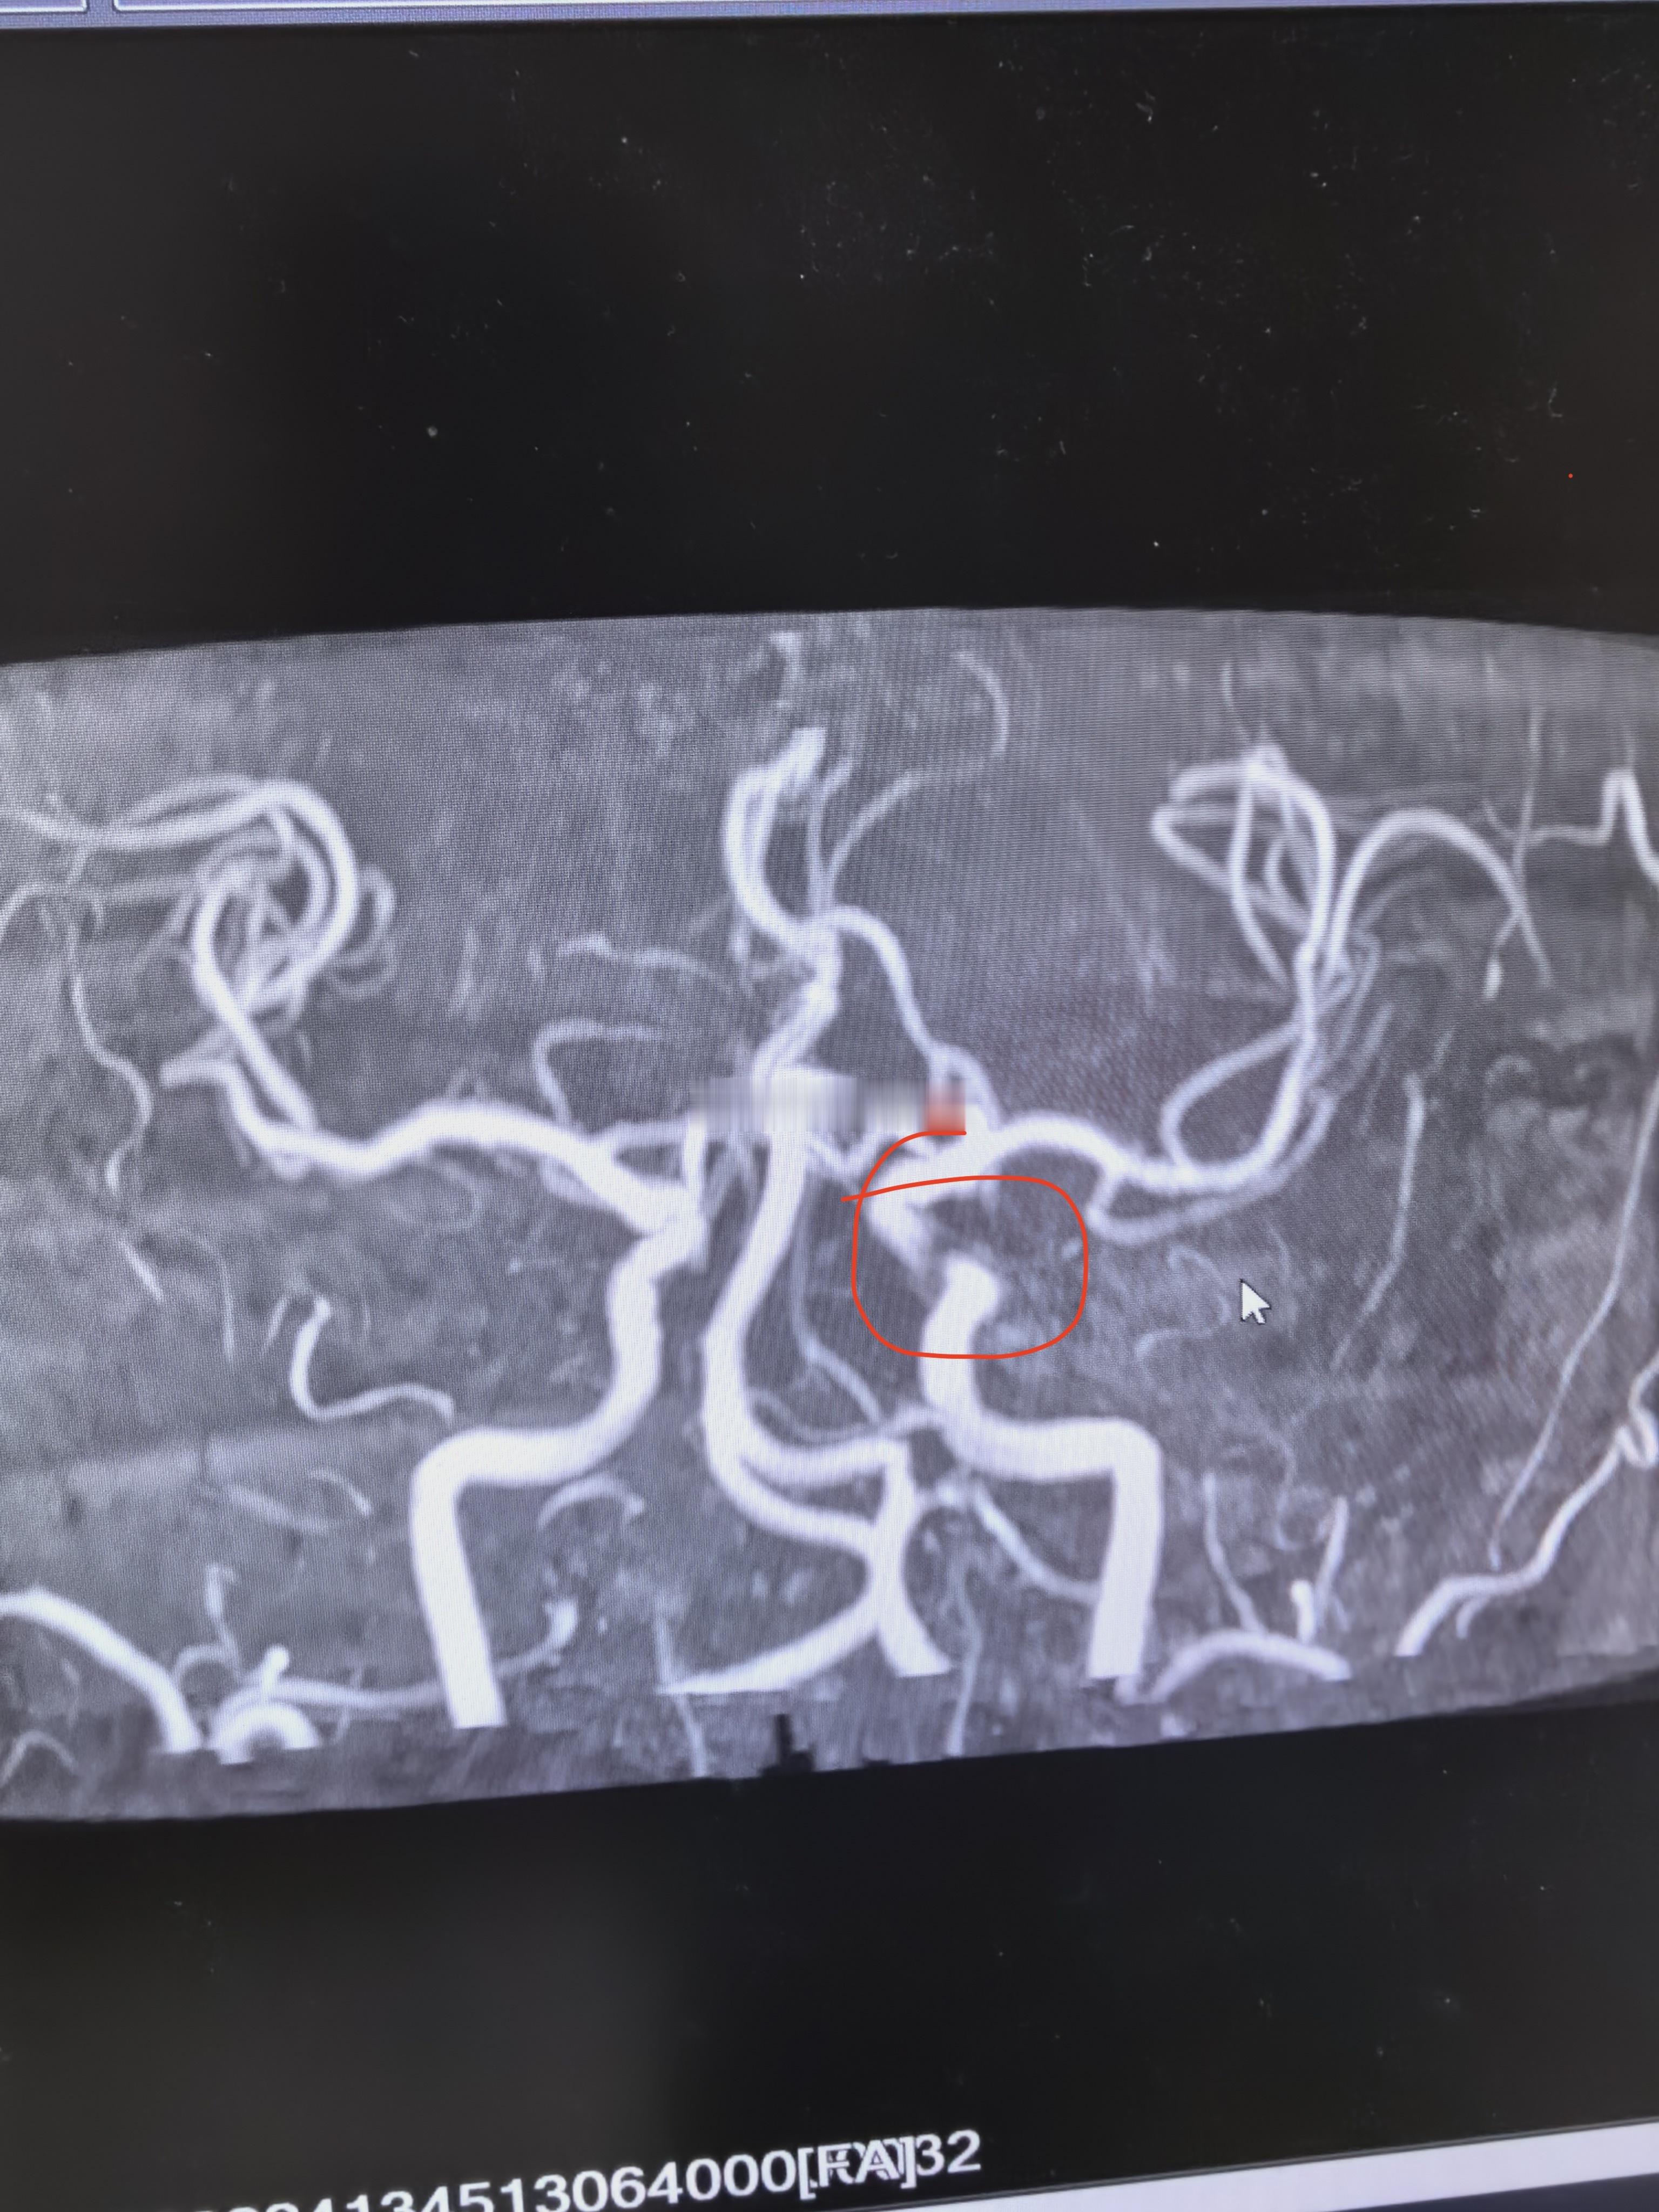

左侧颈内动脉可见一处狭窄,看了下患者2023年的片子,当时没事。